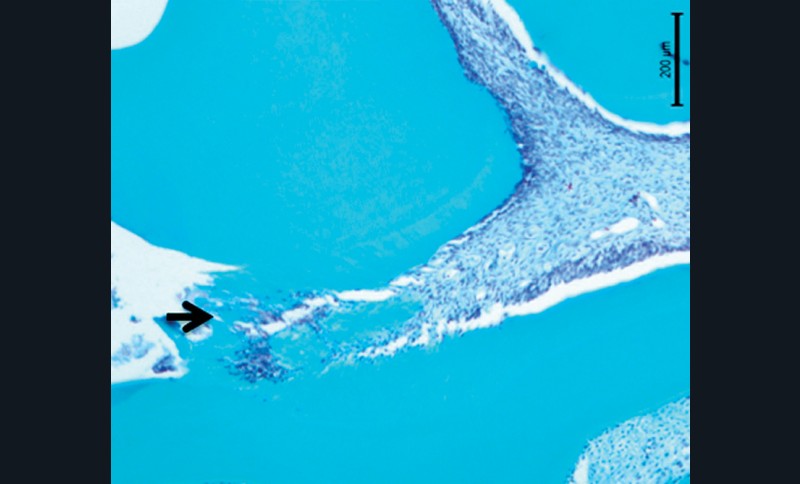

Il est connu depuis longtemps, qu’une pulpe exposée est capable de conserver sa vitalité dès lors que les conditions biologiques et cliniques sont réunies pour qu’un pont dentinaire se forme en fermant la brèche dentinaire présente (1). Le tissu pulpaire ainsi isolé recouvre alors son état de santé et ses fonctions (fig. 1).